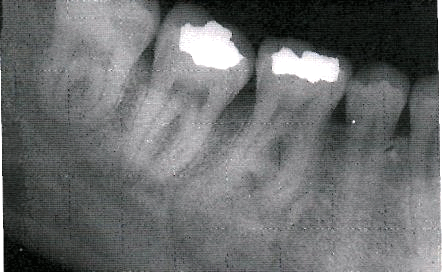

Рентгенологическая картина. Фиброма проявляется в виде гомогенного разряжения костной ткани округлой формы с относительно четкими границами. Патологический очаг окаймлен истонченным слоем кости без периостальной реакции. В центре очага могут быть участки петрификации.

Рентгенологическая картина. Определяется очаг деструкции костной ткани с нечеткими границами. В некоторых случаях может иметь вид мелких ячеистых образований, разделенных костными перегородками.

Рентгенологическая картина опухолевых поражений челюстных костей немногочисленна, это деструкция, деформация кости и периостальная реакция. Деструкция наблюдается в виде одиночного (фиброма, миксома, энхондрома, остеобластокластома, остеогенная саркома и др.) и множественных очагов (эозинофильная гранулёма, полиоссальная фиброзная дисплазия). Форма очагов деструкции может быть округлая, продолговатая, неправильная, очаги деструкции могут локализоваться в любом участке кости челюсти, располагаясь центрально или периферически.

Характер границ довольно типичен: так, остеома является прямым продолжением кортикального слоя и сливаясь с ним, располагается на поверхности кости. Очаг фиброзной дисплазии, располагаясь внутрикостно, имеет обычно четкую границу в виде склеротической каемки.